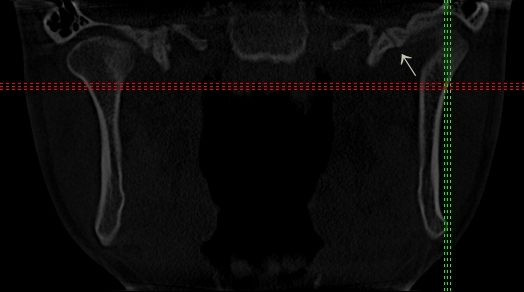

Streszczenie: W pracy opisano występujące u pacjentki i trwające od 8 lat dolegliwości w postaci szumów usznych. Pacjentka przed zgłoszeniem się do Poradni Protetyki Stomatologicznej i Dysfunkcji Narządu Żucia Śląskiego Uniwersytetu Medycznego w Katowicach była leczona interdyscyplinarnie – bez zadowalających rezultatów. Przeprowadzono wnikliwe badanie układu ruchowego narządu żucia i zastosowano terapię szyną okluzyjną.

Summary: The paper presents a case study describing a patient with tinnitus, lasting for 8 years. Before referring to the Department of Temporomandibular Disorders, SMDZ Unit in Zabrze, SUM in Katowice, Poland, the patient was treated interdisciplinary – without satisfactory results. A thorough functional examination of the stomatognathic system was carried out and treatment with occlusal splints was introduced.